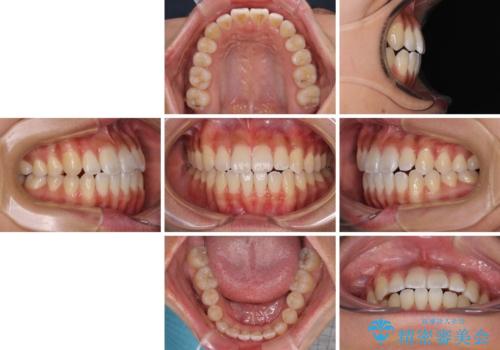

急速拡大装置で上顎骨を十分に拡大できたことで、非抜歯で八重歯を歯列に納めることができました。

患者様はもちろん、我々もここまで綺麗に仕上げられるとは想像もできず、お互いに大変満足な治療となりました。